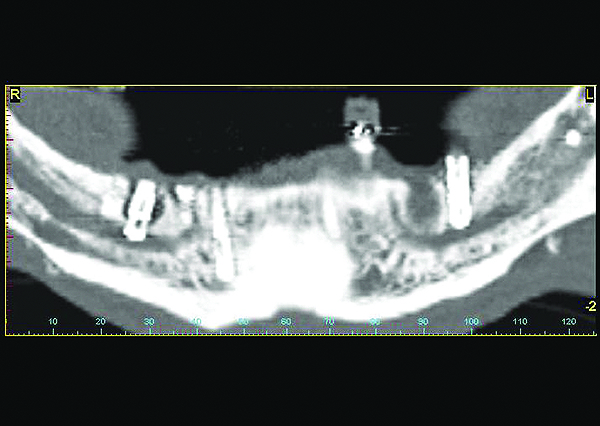

Computerized axial view of the implant in Fig 5 showing the buccal bone loss and exposed implant surface.

Figure 6

Two implants which damaged the inferior alveolar nerve causing irreversible bilateral numbness in the lip, soft tissues, and teeth innervated by this branch of the mandibular nerve. This is considered a major complication.

Figure 7